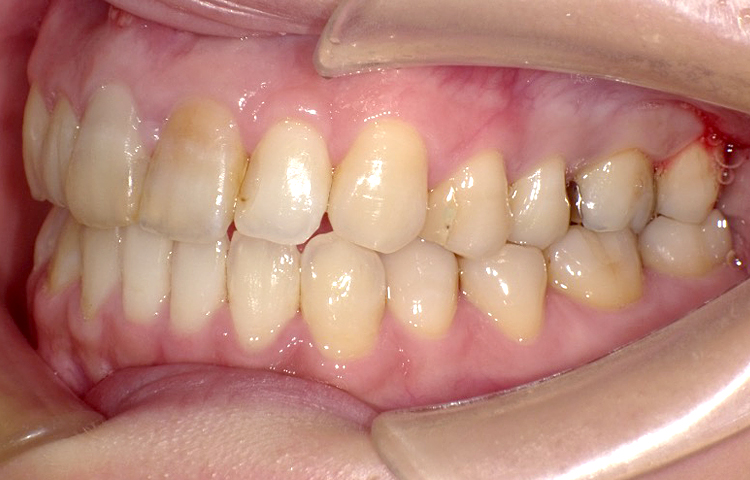

症例5

治療前

治療後

| 主訴 | 右上1番下げたい 1.1間隙間うめたい 上のみ部分矯正希望 |

|---|---|

| 治療 期間 |

約7ヶ月 |

| 治療費 | 175,000円(税込)/調整費用別途 |

| 治療 内容 |

上の前歯部にワイヤーを着けて進めていく、プチ矯正で施術。 |

| 治療の リスク |

奥歯を動かさないので前に出して並べていく。 歯を動かすことで、歯茎が下がるリスクある。 装置による清掃の難しさから、歯肉炎や歯周病、虫歯のリスクが高まる。 矯正終了後は、リテーナーを使用し、後戻りを防ぐ必要がある。 |